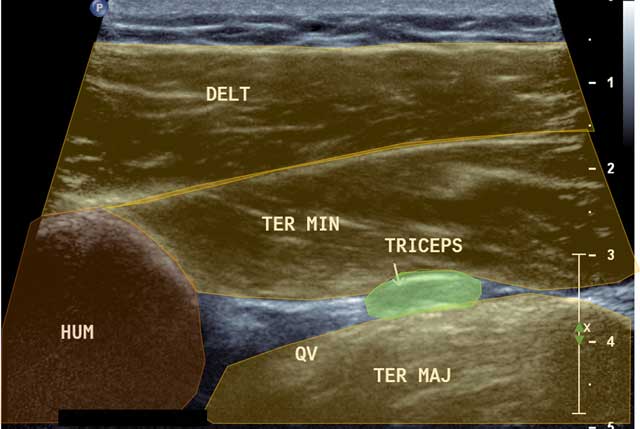

Figure 6

Focus in axial view of the quadrilateral space. HUM: Humerus, DELT: Deltoid muscle, QV: Quadrilateral Velpeau Space, Ter Maj: Teres Major, Ter Min: Teres Minor, Triceps: Tricipital muscle.

Both the posterior circumflex artery and the axillary nerve are held inside. The axillary nerve belongs to the posterior bundle of the Brachial Plexus and provides motor innervation of the Deltoid and Teres Minor and sensory innervation of the stump of the shoulder. It goes from the subscapular muscle and the axillary artery to the Velpeau Quadrilateral Space [678].

To analyze and locate the Velpeau Quadrilateral Space, a posterior axial cross section centered onto the Triceps Brachii tendon with the arm along the body in internal rotation (starting from an axial cross section performed in the Teres Minor axis) is needed.